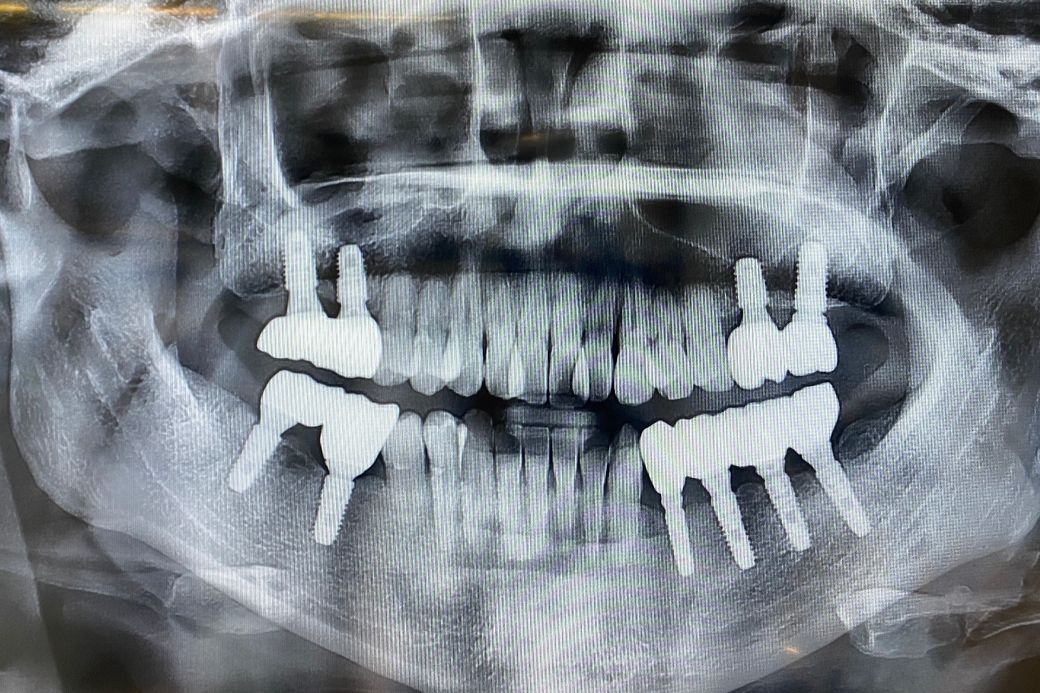

최근에 엑스레이를 찍어 보았는데, 뼈부분의 소실은 크게 보이지 않아 괜찮다고 하셨는데 그래도 나이가 들 수록 점점 잇몸이 내려갈텐데 더 내려갈까봐 걱정입니다. 혹시 잇몸재생주사 (연어주사)를 맞으면 임플란트 주변에 잇몸이 다시 차오를까요? 아님 주사보다 잇몸이식을 해야하나 걱정입니다

(아래사진= 2025년 4월에 찍은 엑스레이)

엑스레이 사진 상 잇몸뼈 낮지 않습니다 잇몸 재생이나 잇몸주사 필요할 정도는 아니라고 봅니다 그냥 평상시 위생관리 잘해주세요 임플란트도 기능상 문제 없습니다